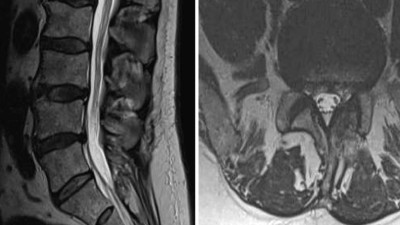

Chronische Schmerzen nach Wirbelsäulen-Op.? So gehen Sie vor

Ein „Persistent Spinal Pain Syndrome Typ 2“ ist alles andere als selten – die Betroffenen leiden unter anhaltenden oder wiederkehrenden starken Dauerschmerzen und Funktionseinschränkungen nach einer Wirbelsäulen-Op. Wer profitiert von konservativen Maßnahmen, wann ist eine Reoperation angezeigt, und bei wem stellen neuromodulative Verfahren eine Alternative dar?

Durch das Foramen an die Nervenwurzel

Epidurale Injektionen gehören zu den am häufigsten durchgeführten Interventionen bei Bandscheibenvorfällen. Mit einer transforaminalen Injektion (periradikuläre Therapie) ist es möglich, gezielt eine Nervenwurzel zu erreichen. Wichtig für gute …